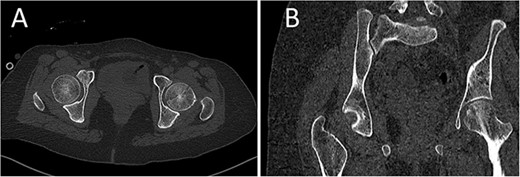

A medically free 42-year female presented to our institute as a life-saving case from a different hospital as she was a victim of unrestrained road traffic accident 2 days prior to presentation. Upon assessment in the emergency department (ER), she was conscious and oriented, and was found to have bilateral lung contusion, and multiple fractures of ribs. She also had a left sided vertical femoral head fracture dislocation comprising around 40% of the femoral head (Fig. 1). Closed reduction under conscious sedation was done in the ER, which was successful based on post-reduction imaging studies (Fig. 2). Her chest injuries were treated with chest tube and observation for 10 days. During that time, discussion was made with the patient regarding her situation and conservative management was chosen by way of bed rest and continuation of skeletal traction for 4 weeks with serial radiographs in the hospital on a weekly basis after clearance of her chest injuries. Skeletal traction was discontinued and she was advised to continue bed to wheelchair mobilization for an additional 2 weeks. After 6-weeks from the injury, a Computed Tomography (CT) was done to the patient and revealed signs of fracture healing (Fig. 3). At 3-years after the injury, she was found to have full painless range of motion of the affected hip and has resumed her activity of daily living without any complaints and the images showed a symmetrical joint space of the hips (Fig. 4).

CT scan of the pelvis showing axial (A) and coronal (B) cuts at 6-week post-injury showing signs of healing of the left fractured femoral head with a concentric hip joint.

Yoon et al. proposed that small or comminuted Pipkin I require surgical excision, whereas large fragments typically require anatomical fragment reduction and fixation [10]. What made us consider offering conservative treatment is that the fragment was anatomically reduced in postreduction computed tomography (CT) scan. Another reason that could have helped at maintaining the reduction is the vertical nature of the fracture, whereas if it was oblique or horizontal, shear forces produced by hip abductors would have displaced the fracture. Moreover, in the prereduction trauma CT, the fragment was found to be positioned well in the corresponding acetabulum likely restrained by iliopsoas, indirect head of the rectus femoris, and the capsule [11]. The patient was followed on a weekly basis with radiographs while on skeletal traction.